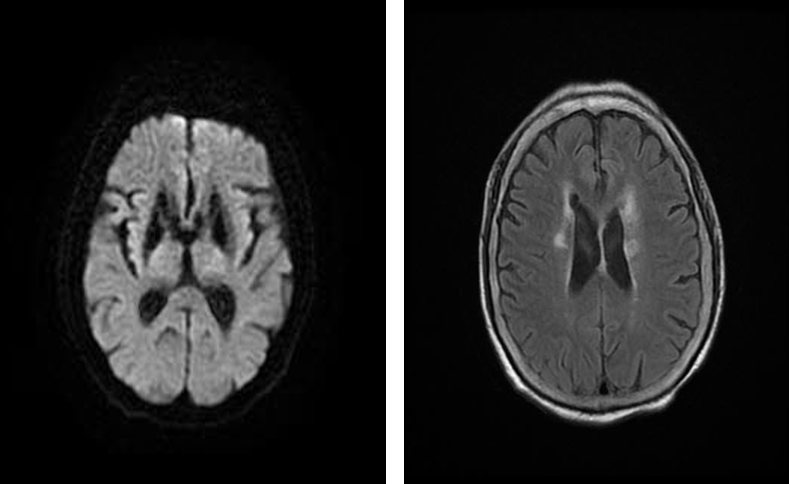

◆ 左侧颈内动脉C4段重度狭窄。

导丝怎么扩重磅!NOVA颅内药物球扩支架湖北首例植入!_https://www.jmylbn.com_新闻资讯_第8张

左侧颈内动脉造影

◆ 导引导管置于左侧颈内动脉C1段,微导丝通过狭窄段置于左侧大脑中动脉M2段。

导丝怎么扩重磅!NOVA颅内药物球扩支架湖北首例植入!_https://www.jmylbn.com_新闻资讯_第9张

导引导管到位,导丝通过病变

◆ 沿微导丝将3.0*15mm赛诺神畅 NOVA颅内药物球扩支架定位在颈内动脉狭窄处。

导丝怎么扩重磅!NOVA颅内药物球扩支架湖北首例植入!_https://www.jmylbn.com_新闻资讯_第10张

NOVA支架到达病变部位